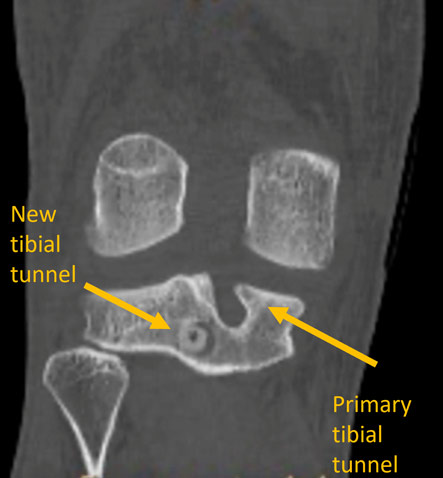

Post-op CT-Scan

• New anatomic tibial tunnel